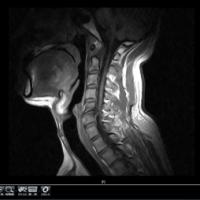

フォロー ブログを報告 登録ID 1921619 タイトル 電子書籍作家「良歌の宮」は障がい者! URL http://ameblo.jp/ryoukanokimi/ カテゴリ アメリカン・ショートヘア (24位/113人中) 脊髄損傷 (1位/7人中) 紹介文 障がい者ってなってみて始めて分かる大変さ。毎日ころころ変わる体調に振り回されながら私は物書き女。障がい者になった女はいらんと捨てられたことは糧になった。 登録:2017年07月(8年) 1日数回 5 記事一覧